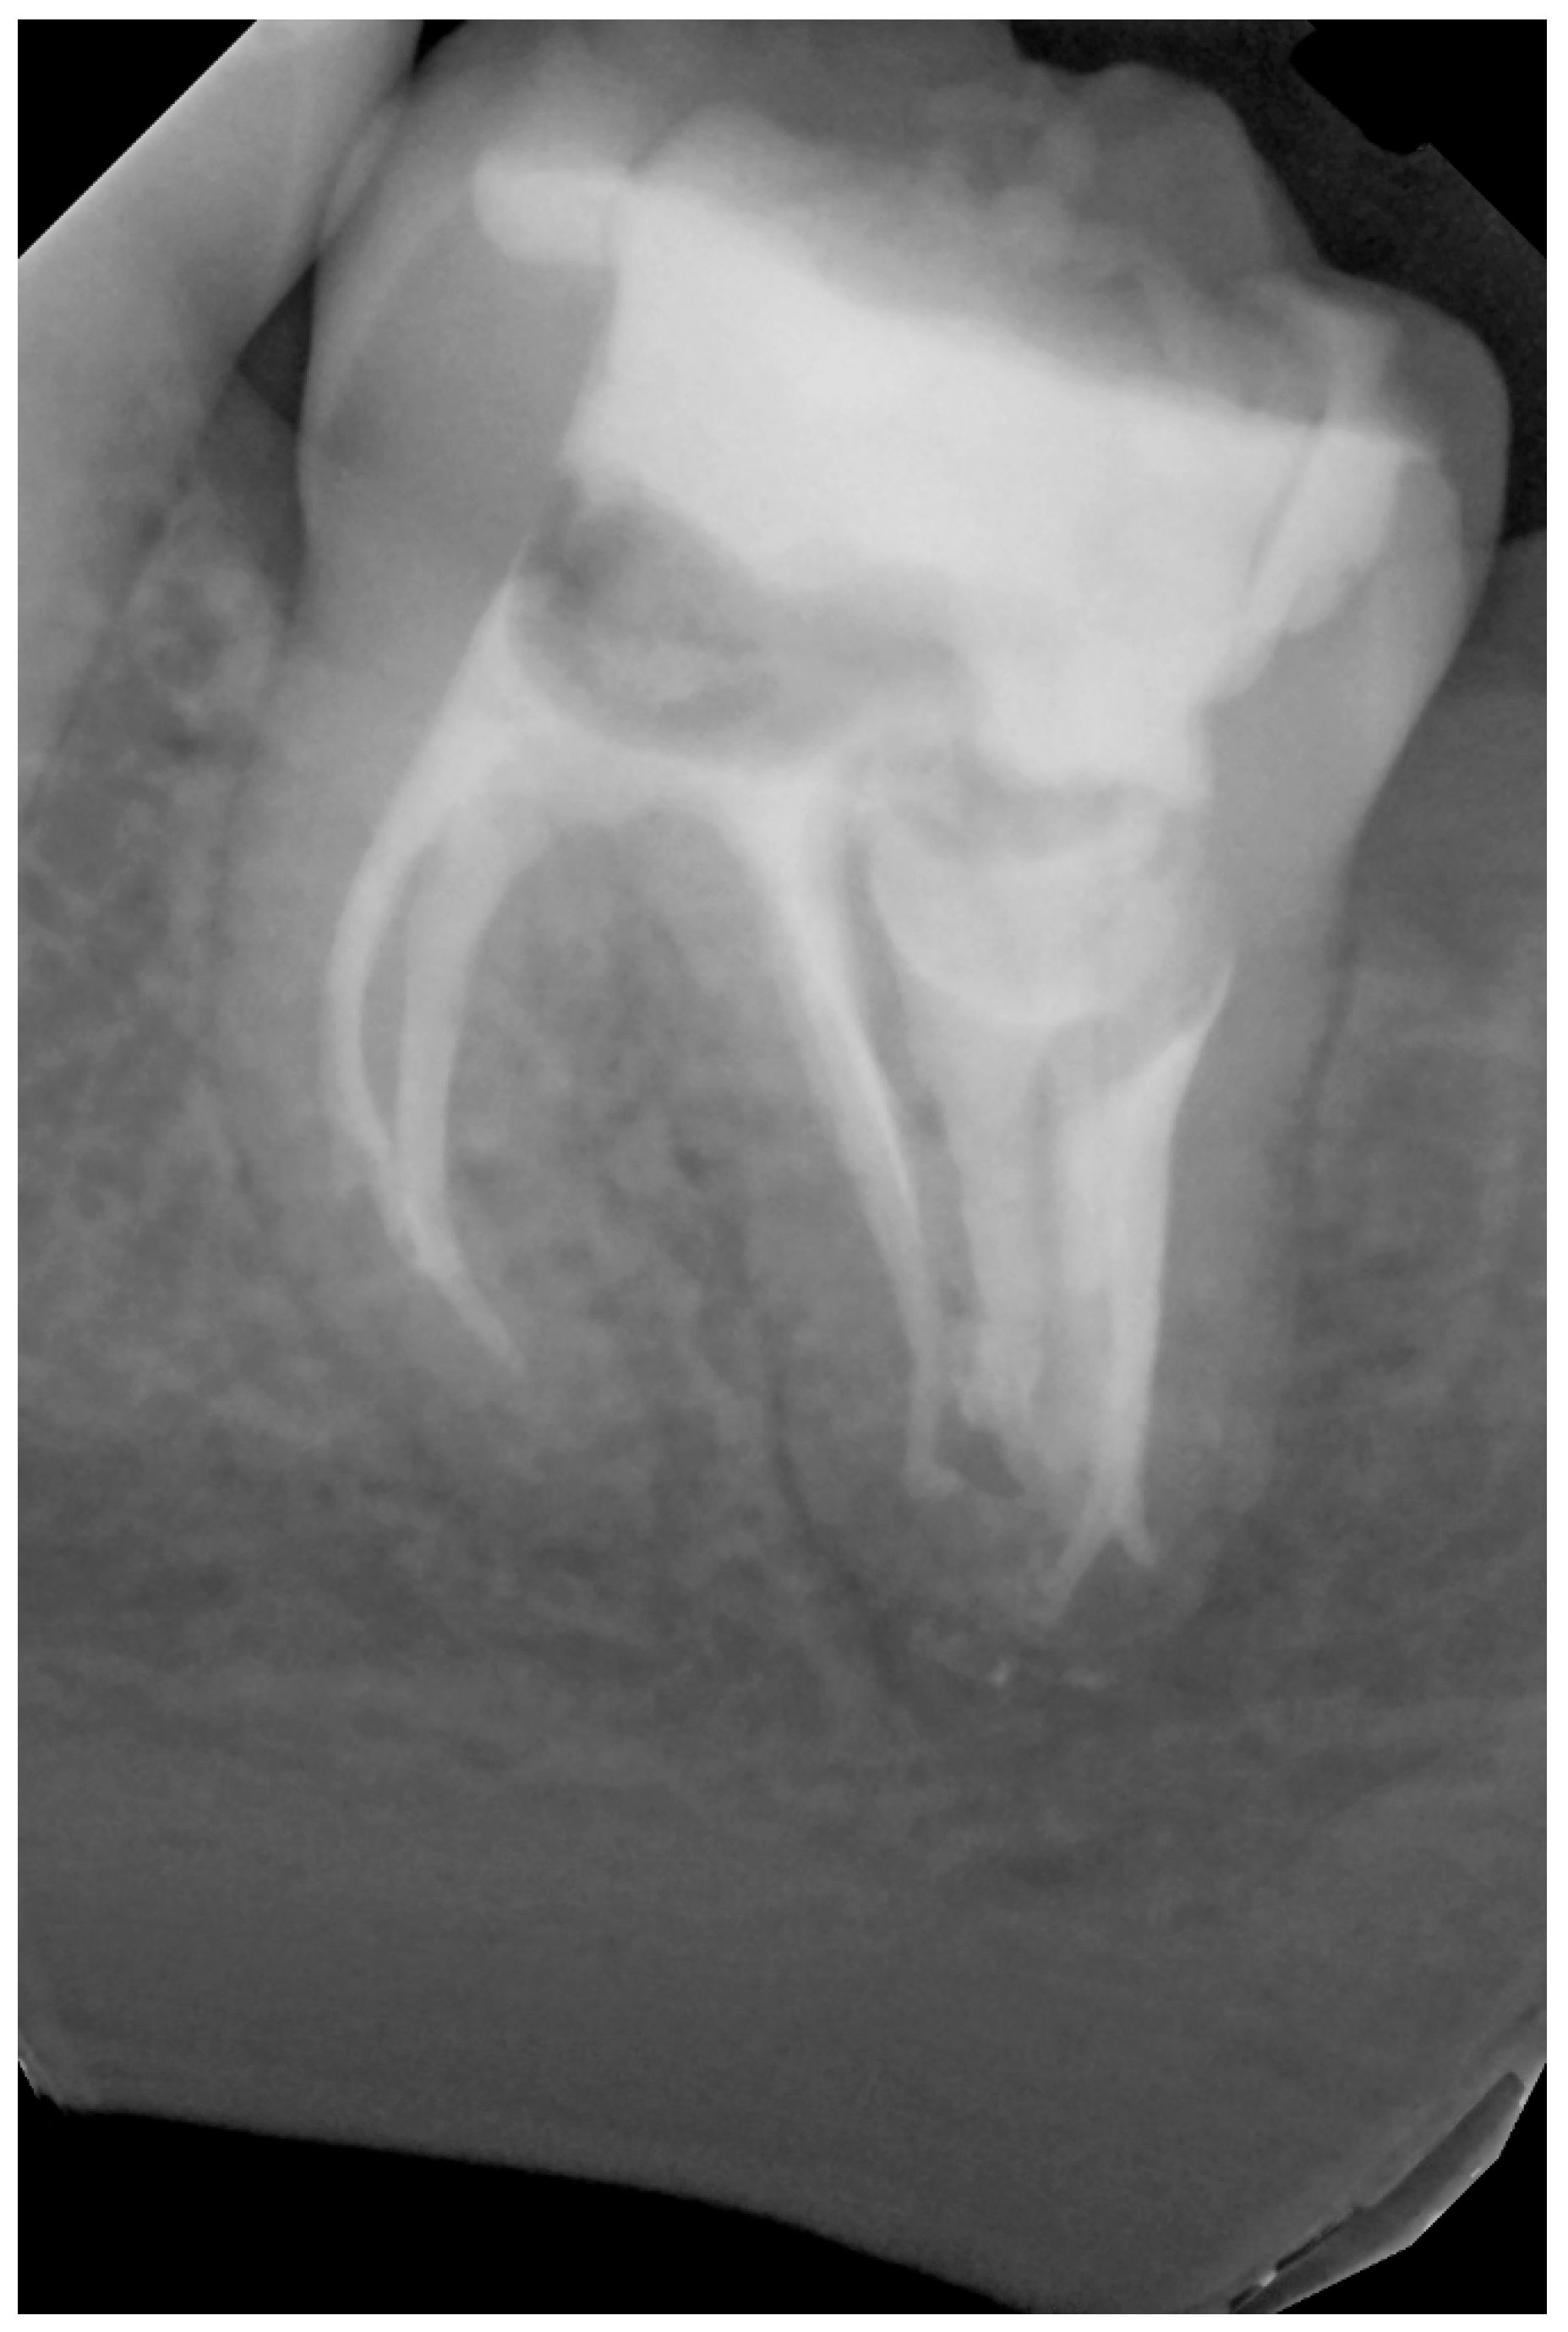

2. Case Presentation

2.1. The First Visit

2.2. The Second Appointment

2.3. The Third Appointment

2.4. The Fourth Appointment

2.5. The Fifth Appointment

2.6. Sixth Appointment